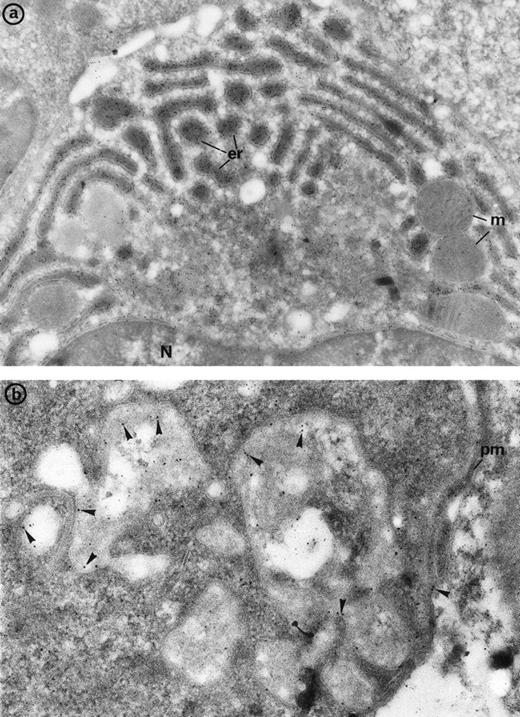

Electron microscopy confirmed the diagnosis of erythroblastic synartesis in the 3 patients. Plasma membranes of adjacent erythroblasts were joined by closely interdigitating processes (Fig2). Cytochemical demonstration of the peroxidatic activity of hemoglobin (not shown) allowed identification of maturation stages of the erythroblasts, because its level of intensity relates to the hemoglobin content of each cell. This technique showed that erythroblasts of the same maturation stage, as well as those of different maturation stages, were linked. Ribosomes were absent at sites of linkage via interdigitating process, corresponding with the nonbasophilic areas observed by light microscopy (Fig3a). At the junction sites, coated pits and rhopheocytosis vesicles were absent, probably because a macrophage expansion would find it impossible to penetrate this zone of tightly linked plasma membrane. Ferritin granules were never observed within these junctions. Junctions between erythroblasts had a characteristic morphology: resembling gap junctions, they were formed by 2 closely placed membranes joined by periodical structures every 150 Å, giving rise to a zipper-like appearance (Fig 3b). Isolated normoblasts often displayed picnotic nuclei and/or binuclearity. The 2 external leaflets of the plasma membrane of adjacent erythroblasts were separated by a constant space of 145 Å in patient 1, and 180 Å in patients 2 and 3.

The electron microscopic aspect of the bone marrow erythroblasts from patient 1: Cells are joined by interdigitating processes of the plasma membrane (arrowheads). They delineate areas of cytoplasm which are deprived of ribosomes (N, nucleus; m, mitochondria). Original magnification: ×21,000.

The electron microscopic aspect of the bone marrow erythroblasts from patient 1: Cells are joined by interdigitating processes of the plasma membrane (arrowheads). They delineate areas of cytoplasm which are deprived of ribosomes (N, nucleus; m, mitochondria). Original magnification: ×21,000.